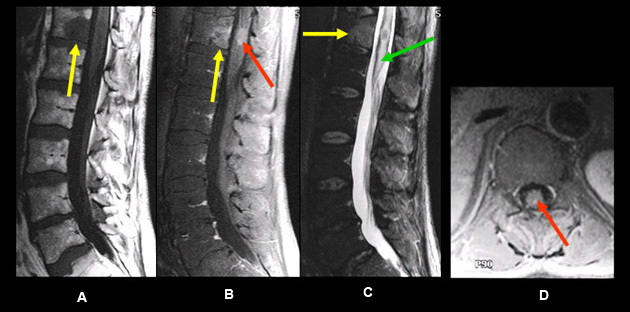

Imaging findings: Figure 3

- Pre-contrast sagittal T1wtd. MRI

- yellow arrow points to an intradural ventrally located tumor producing thoracic cord compression.

- Post-contrast sagittal T1wtd. MRI

- tumor enhances with contrast (yellow arrow)

- Sagittal T2 wtd. image

- calcified nature of the tumor is identified as an area of dark signal intensity (yellow arrow)

- Pre-contrast axial CT

- yellow arrow points to an area of high CT attenuation density consistent with calcification

- red arrow points to displacement of thoracic cord to the right side

Final impression :

- An intradural extramedullary enhancing tumor.

- Ventrally located tumor has produced cord compression with displacement of the thoracic cord to the right side.

- Calcified nature of the tumor is identified on sagittal T 2 wtd. image as an area of dark signal intensity and confirmed by CT imaging as an area of high attenuation density.

Findings are consistent with meningioma.